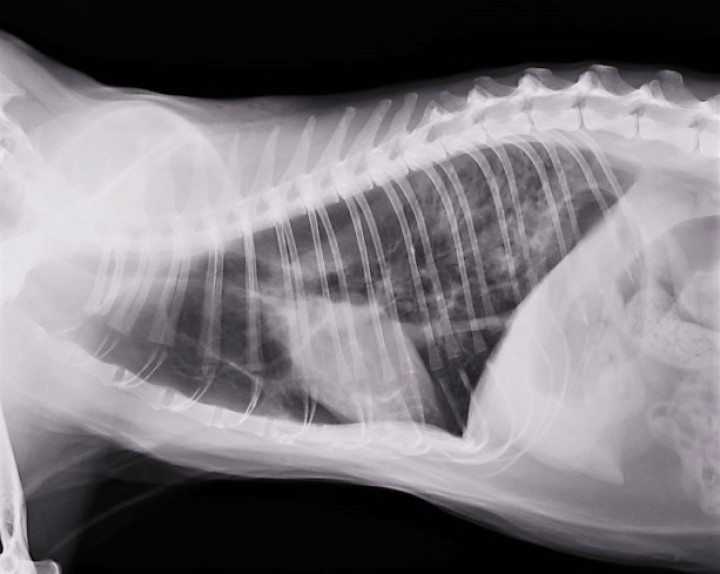

Se realiza radiografía torácica dorsoventral (Fig. 3), en la que se observa el pulmón derecho hiperinsuflado, con desplazamiento lateral del corazón hacia el lado izquierdo. El pulmón izquierdo presenta marcada reducción de volumen por hipoinsuflado, con presencia de alveogramas, regiones atelectásicas y una aparente bulla. Ante estos hallazgos y la pobre respuesta al tratamiento médico, se propone la realización de más pruebas diagnósticas, como una Tomografía Computarizada (TC) de tórax y/o toracotomía exploratoria. Ante la alta probabilidad de requerir un tratamiento quirúrgico posterior, los propietarios deciden realizar la toracotomía exploratoria por ser un método que permite simultáneamente implementar medidas diagnósticas y terapéuticas.

<div class=\"Basic-Text-Frame\">

<p>Radiografía de tórax dorsoventral. Desviación del corazón hacia lado izquierdo del tórax por atelectasia completa de pulmón izquierdo, que presenta patrón intersticial-alveolar y una posible bulla enfisematosa en polo caudal. Pulmón derecho hiperinsuflado. L: izquierda.</p>

Figura 3

Radiografía de tórax dorsoventral. Desviación del corazón hacia lado izquierdo del tórax por atelectasia completa de pulmón izquierdo, que presenta patrón intersticial-alveolar y una posible bulla enfisematosa en polo caudal. Pulmón derecho hiperinsuflado. L: izquierda.